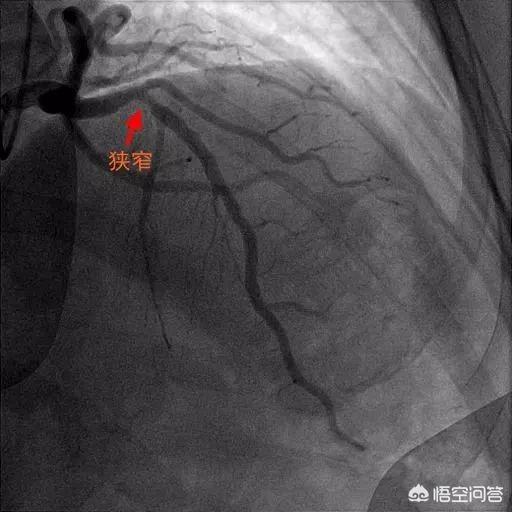

まず心臓の血管の狭窄の程度を見てみよう:

第一度狭窄:冠動脈の25~49%の狭窄。 一般にこのような狭窄は冠動脈性心疾患とは呼ばず、冠動脈アテローム性動脈硬化症と呼ぶ。

グレード2の狭窄:冠動脈の50~74%の狭窄。 この程度の狭窄であれば、狭窄が狭くなっても血流は心臓に十分であり、通常は症状を引き起こさないため、ステント留置術やバイパス手術は通常必要ない。

グレード3の狭窄:冠動脈の75-99%の狭窄、従来の標準によると、この程度の狭窄のほとんどは、再建、つまりバイパス移植やステント治療を学ぶ必要があります、もちろん、まず第一に、我々は薬物療法を制御する必要があり、薬物治療の効果に基づいて、ステントやバイパス移植を考慮することは良くありません。

クラスIVの狭窄:100%の冠動脈狭窄、つまり完全な閉塞、これは心筋梗塞であり、もちろんそのほとんどは急性心筋梗塞であり、血栓溶解療法であれステント留置術であれ、蘇生が必要である!

狭窄はどのように計算するのですか?

実際、75%の狭窄や50%の狭窄というのは、医師の経験と多角的な画像診断の結果に基づいて導き出された結論に過ぎず、厳密には多少の誤差があるかもしれない。例えば、私が70%と言ったのに医師が80%と言ったとしても、何の問題もない。